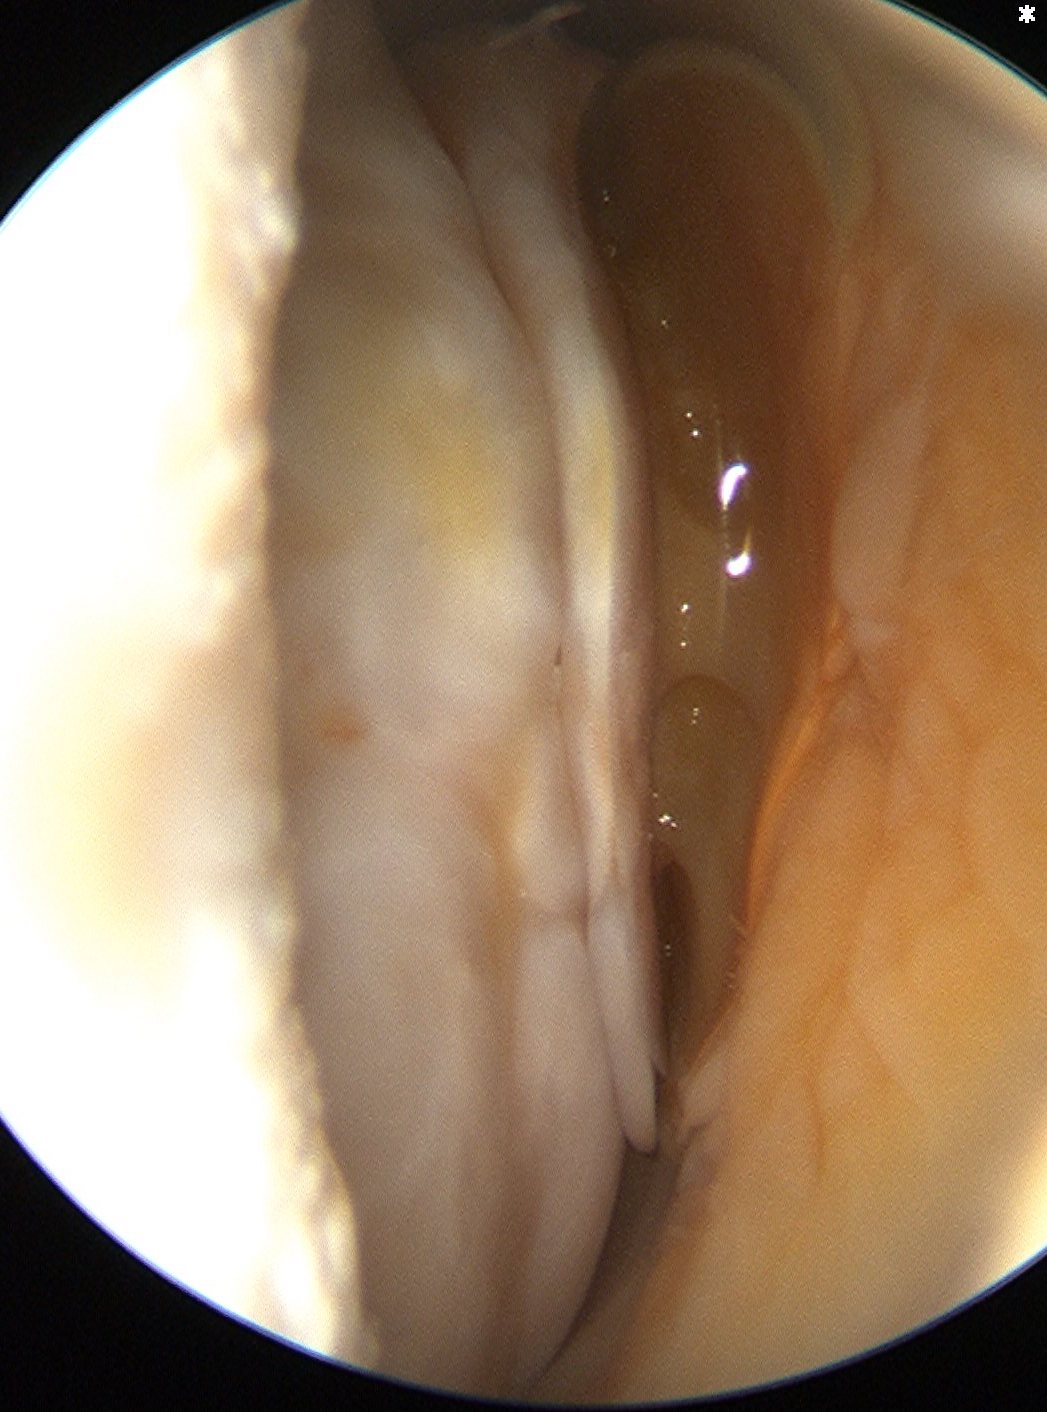

Variations in anterior labral anatomy above equator

| Sublabral foramen | Sublabral foramen with cord like MGHL | Absent labrum with cord like MGHL |

|---|---|---|

| Buford complex | ||

|

|

|